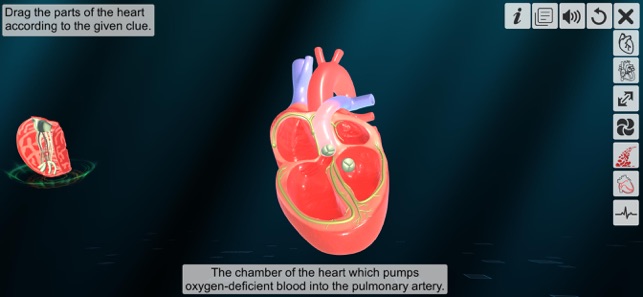

4. Assemble of chambers.

‘Heart - An incredible pump’ app explains the external and internal structure of human heart through the simulation 3D model to improve the comprehension of the topic. The user can interact with the 3D model by tapping the model and getting acquainted with the particular part of the human heart. Tapping the model displays the name of the part and also the simulation module is appropriately supported with in depth information about each external and internal structure part.